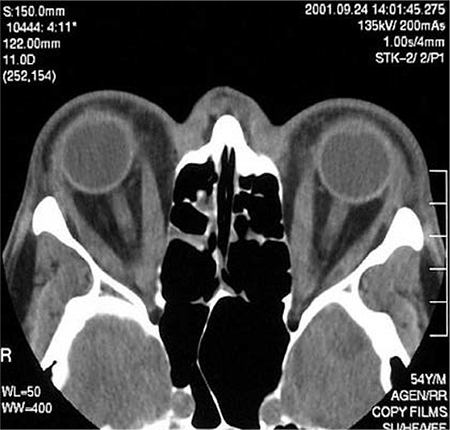

Request cross-sectional imaging of the orbit (i.e., CT or MRI scan) in patients with euthyroid unilateral orbitopathy, or other atypical presentations (e.g., no previous or present evidence of thyroid dysfunction, absence of upper eyelid retraction, divergent strabismus, diplopia sole manifestation, history of diplopia worsening towards the end of the day); demonstration of typical muscle thickening is needed in order to rule out other diagnoses.[34]Perros P, Neoh C, Dickinson J. Thyroid eye disease. BMJ. 2009 Mar 6;338:b560.

[Figure caption and citation for the preceding image starts]: Axial CT scan through the orbits of a patient with Graves orbitopathy showing increased thickness of medial rectiCourtesy of Dr Petros Perros [Citation ends].